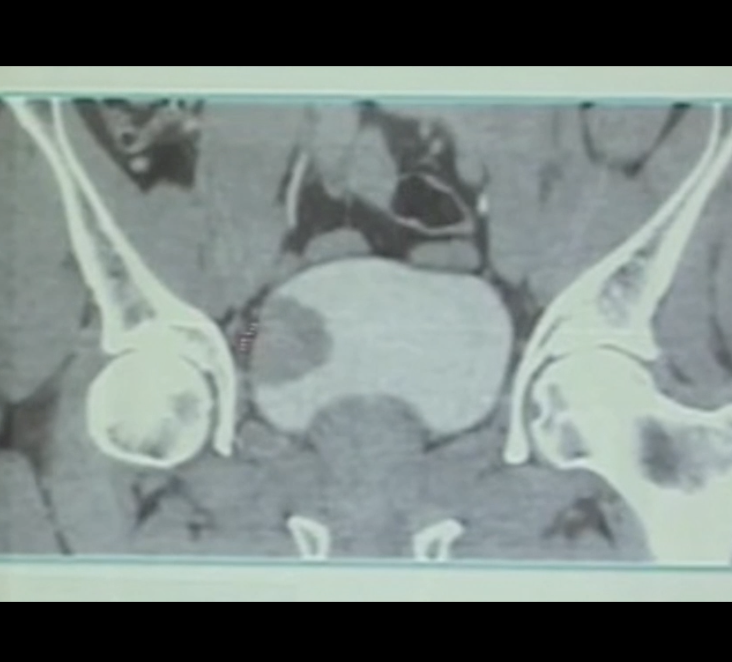

Conversion to Laser Enbloc Resection following complicated TURBT

Obturator kick is not infrequently reported during conventional transurethral resection of bladder tumor. Unfortunately, it may end with bladder perforation and hardly controllable bleeding. Herein comes the role of laser ERBT #TURBT #Bladder_tumor #enbloc #erbt #NMIBC